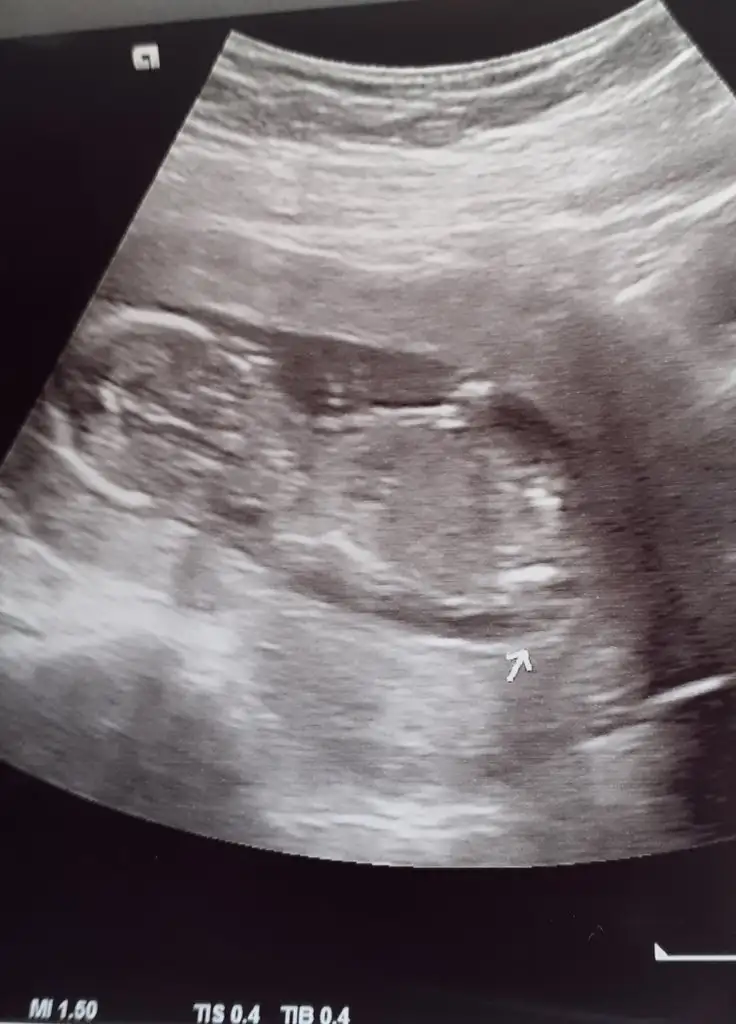

Fazla hareketli değildi bu sefer ayaklarınıda hiç açmadı cinsiyet öğrenemedik yine

Ya çok hareketliydi, böyle kendini geriye doğru atıp durdu.

Elini bi ara ağzına doğru götürdü.

Kadın o kadar detaylı inceledi ki, en sonunda diyo ki güzel de bi görüntü alamadık ama.

Incık cıncık baktı yine.